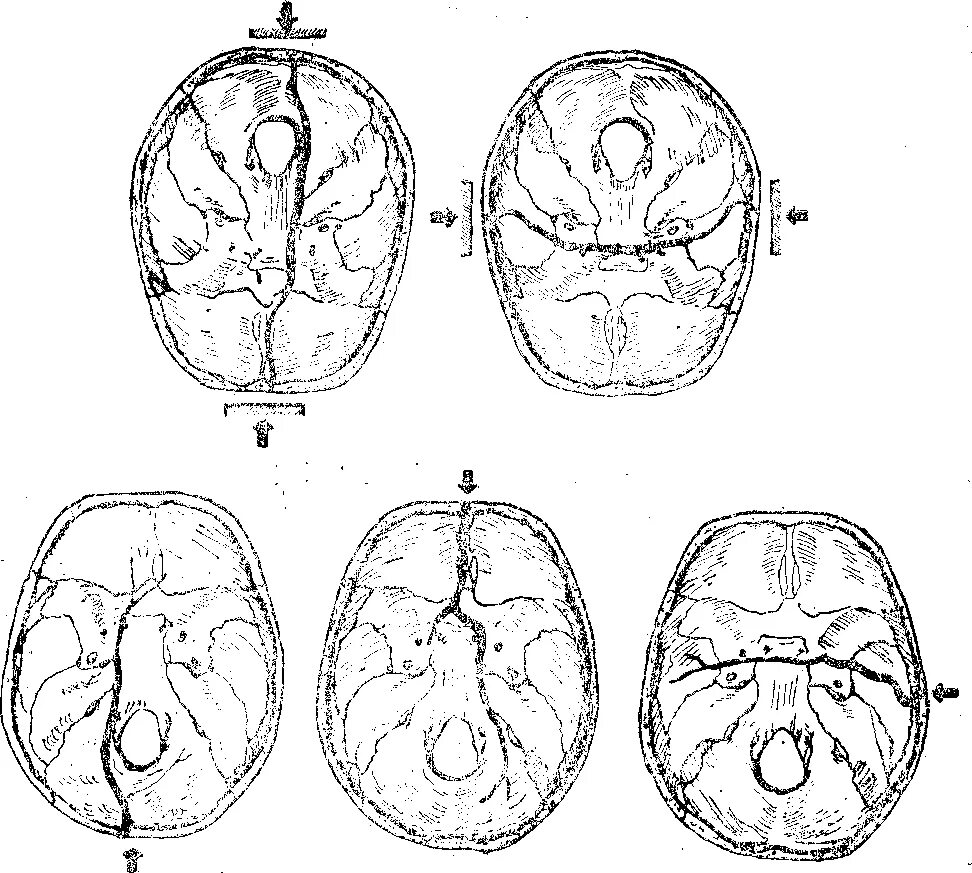

Оскольчатый перелом черепа